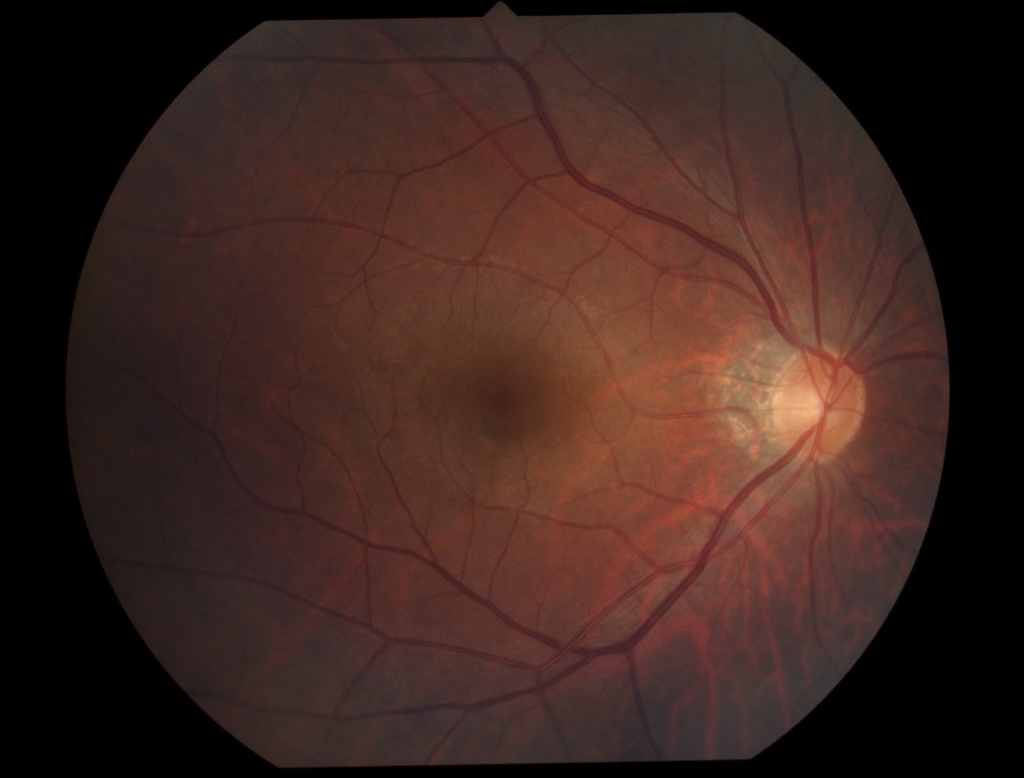

黄斑耳側の網膜表面に膜組織による高反射がみられ、血管が蛇行し偏位がみられる。